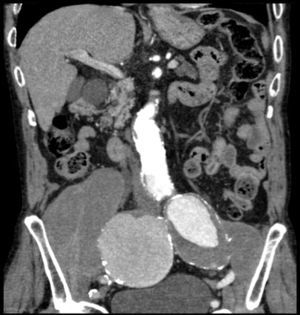

Paciente varón de 86 años, hipertenso en tratamiento con 2 fármacos, con historia de dolor lumbar con irradiación crural derecha de varios meses de evolución que se había controlado parcialmente con tratamiento sintomático. Su reumatólogo le había prescrito RM dorsolumbar que no llegó a realizarse ya que el paciente acudió antes a urgencias por aumento de la intensidad del dolor. En la analítica, hemoglobina 8,4g/dl, LDH 318 U/l, creatinina 1,29mg/dl, PCR 6,16mg/dl, VSG 24mm/h y leve hipoproteinemia. Ausencia de signos de inestabilidad hemodinámica. Se realizó una TC abdominopélvica con contraste por vía intravenosa que muestra aneurismas ilíacos aislados bilaterales>6cm (fig. 1) con rotura contenida del derecho (fig. 2), que desplazaba el músculo psoas (fig. 3) y horadaba el hueso ilíaco ipsolateral (fig. 4). El paciente es sometido a by-pass aortobifemoral pero lamentablemente fallece en el postoperatorio.

Los aneurismas ilíacos aislados, sin aneurisma aórtico asociado, son raros1. Son relativamente difíciles de identificar, ya que hasta un 40% de ellos se pueden presentar con rotura2. La tasa de incidencia de causas extraespinales de ciática es baja3. Igualmente, el aneurisma roto crónico constituye una entidad peculiar. Todas estas circunstancias se aúnan para que el diagnóstico, la mayoría de las veces, sea erróneo y tardío4. Suele tratarse de una rotura laterodorsal hacia las inserciones anteriores del psoas que contiene el hematoma, evitando la extravasación masiva pero no la infiltración de las raíces del plexo lumbosacro, lo que origina un dolor crónico lumbar con irradiación al miembro inferior5, siendo esta su presentación más frecuente6. El diagnóstico puede realizarse con TC abdominal7, pudiendo también visualizarse en la RM lumbar (corte parasagital)7,8. En cualquier momento de la evolución, el aneurisma puede sufrir una rotura aguda secundaria4. Este caso sirve para recordarnos, en nuestra práctica diaria, que la causa aneurismática puede estar implicada en los síntomas de ciática9.